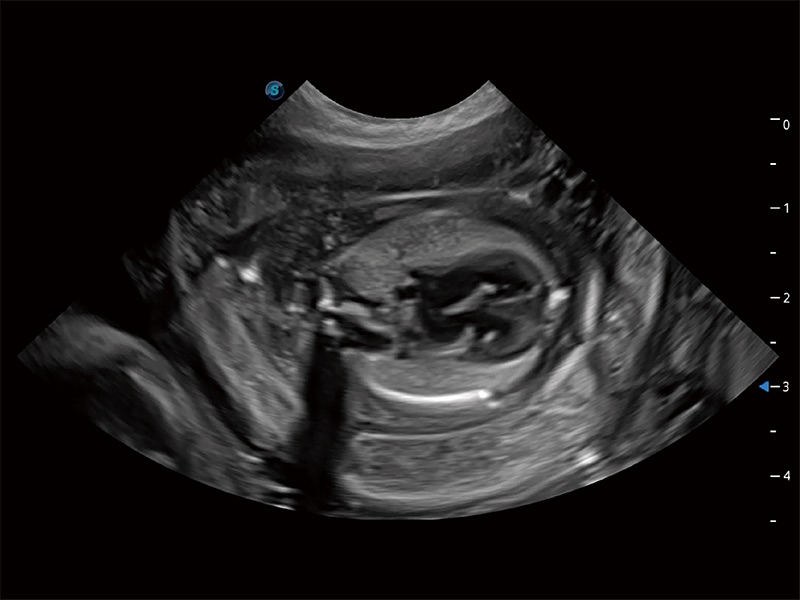

动物是人类最亲密的朋友和最值得信赖的伙伴。球速体育入口也一直致力于探索动物专用的超声影像解决方案。全新推出的ProPet系列,是球速体育入口在动物超声影像智能化、专业化、精准化的一次跨越式革新。动物不能用言语来表述自己的不适,通过超声影像,ProPet系列搭建了动物医生与不同物种沟通的“桥梁”,为动物医生注入了“治愈之力”。 ProPet 80 是球速体育入口匠心打造的一款高端动物专用彩超,采用性能卓越的全新硬件架构,极大提升超声系统的运行效率和数据处理能力,帮助动物医生从容应对日益增多的挑战性病例和日益多样化的临床需求。

高性能和先进的临床应用工具可以为动物医生提供临床信心。ProPet 80 搭载了先进的腹部和浅表应用工具,帮助医生在日常临床实践中发挥前所未有的作用。

ProPet 80 专为动物医生设计,对不同的动物体型和生理结构作出了针对性的优化。通过动物影像专用软件,可满足个性化的应用需求,帮助动物医生获得更精确的诊断数据。